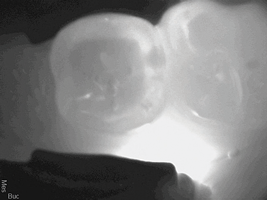

In another case, a 57-year-old patient presented with sensitivity for 6 months on tooth No. 18 which was increasing (Figure 3 and Figure 4). The clinician adjusted it to determine there was no occlusal component compounding the sensitivity. However the patient continued to experience sensitivity. To provide the patient relief, two applications of SDF were recommended. After the first application, which required only 10 minutes, the patient experienced a considerable decrease in sensitivity. A follow-up application of SDF two weeks later resulted in an additional charge for the placement of SDF, which added to the production of the appointment. The patient left with resolution of her complaint.

(3.) Patient presented with sensitivity for 6 months on tooth No. 18.

Figure 3

(4.) Patient presented with sensitivity for 6 months on tooth No. 18.

Figure 4